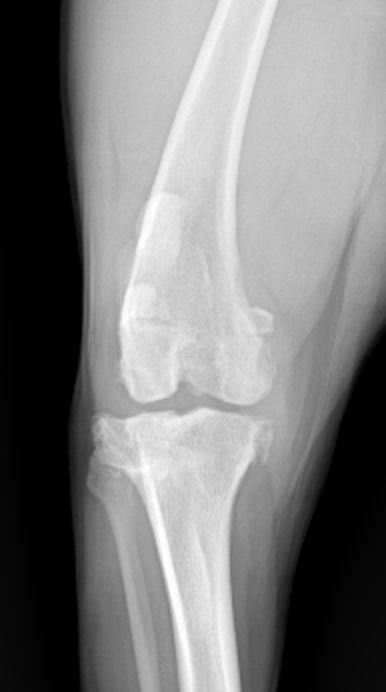

Is Osteoarthritis a young dog disease? Turns out the answer is yes!

Should we consider arthritis a young dog disease! Turns out yes, that is when it starts! Dr. Lindsey Fry’s blog on this topic!